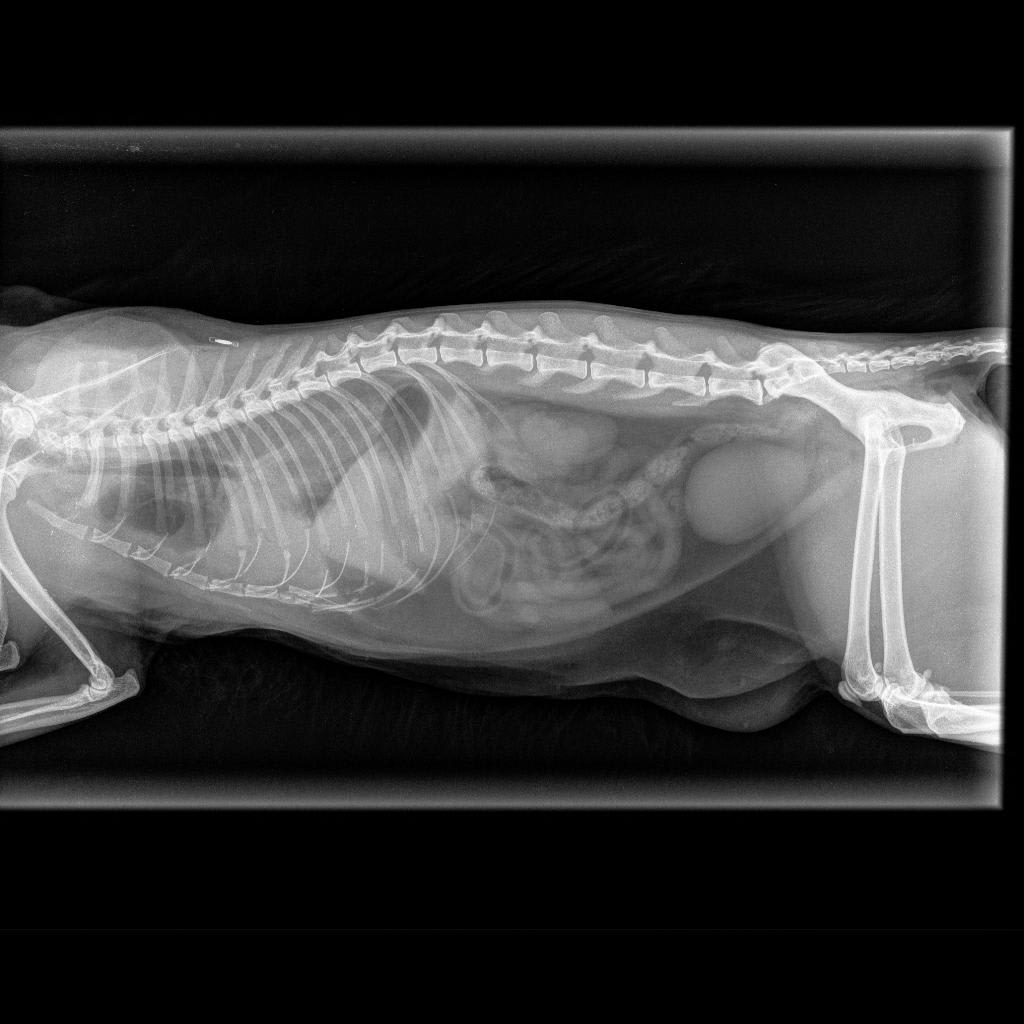

Pet's info: Cat | Domestic Longhair | Female | spayed | 8 years and 7 months old | 8 lbs

Hello, my 8 year old cat was just recently diagnosed with diaphragmatic hernia (unsure when she got it) which is making her eating efforts a bit difficult. She's lost some weight over the past month and will only eat a good meal if I am there to help her. My vet suggested she has surgery as soon as possible, but my mother has knowledge of cats living with the condition just fine and argued my vet may be after money. Since I know this surgery is extremely delicate... Can I get an advice on this?